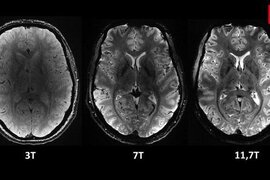

İnsan beyninin ən aydın görüntüsü dərc olunub - VİDEO

Elm adamları insan beyninin ən aydın görüntüsünü dərc ediblər. Şəkli dünyanın ən güclü maqnit rezonans tomoqrafiya (MRT) cihazı ilə əldə etmək mümkün olub. Fotonu Fransa Atom Enerjisi və Alternativ Enerji Agentliyi (CEA) yayımlayıb. Bildirilib ki, "Iseult" adlı MRT cihazı ilə çəkilən şəki